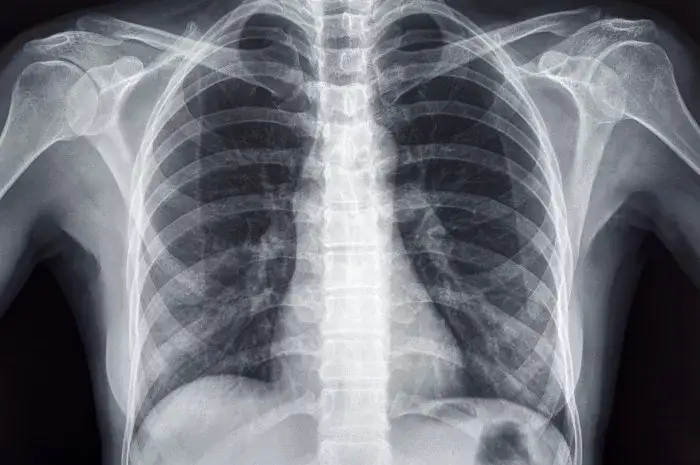

- Zdjęcia rentgenowskie przechowywane poza dokumentacją medyczną pacjenta (np. na kliszach): W tym przypadku termin przechowywania wynosi 10 lat. Liczy się go od końca roku kalendarzowego, w którym wykonano zdjęcie. Warto pamiętać, że dotyczy to klisz, a nie cyfrowych obrazów, które są częścią elektronicznej dokumentacji medycznej.